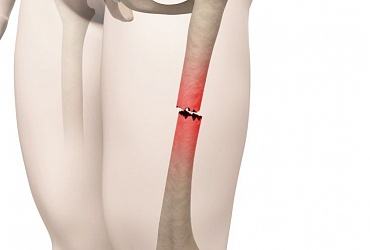

Различают отрыв менисков от места прикрепления к капсуле сустава и разрыв тела мениска. При разрыве мениска оторванная часть сохраняет связь с телом мениска. Такой разрыв называют разрывом мениска по типу «ручки лейки». Чаще возникают разрывы менисков и комбинированные повреждения.

Травматические повреждения менисков могут сочетаться и с другими травмами структур коленного сустава: боковых и крестообразных связок, капсулы сустава. Оторванная часть мениска, связанная с телом мениска может перемещаться в полости сустава и ущемляется между суставными поверхностями бедренной и большеберцовой костей. Возникает блокада сустава, проявляющаяся внезапной резкой болью и ограничением движения в суставе. Особенно часто такая блокада возникает при разрыве внутреннего мениска по типу «ручка лейки».